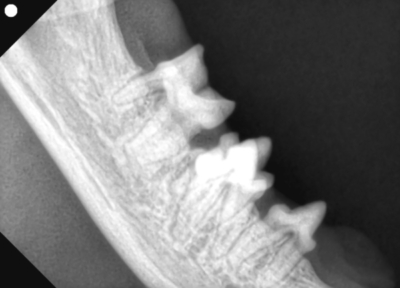

そして歯科レントゲン撮影を行いました。

なにがなにやらわからないと思い、黄色ラインで歯をなぞりました。右上顎です。中央に過剰な歯があり、回転して生えています。

左下顎は正常な数と歯並び

右上顎も同様に中央に回転して生えている過剰歯があります。

左下顎は中央に重なって生えている過剰歯があります。レントゲンで確認しても、乳歯ではなく永久歯と考えられました。これらは過剰歯と呼ばれ、通常より本数が多く歯が生えてきます。かみ合わせが悪くなり、また歯間が狭くなり歯垢がつき、歯周病になりやすいです。そのため、不必要と思われる歯を抜歯しました。また、歯肉の増殖している部分を一部切り取り病理検査用の検体とし、それ以外の部分はメスで切除し正常に近い歯肉の形状に近づけました。